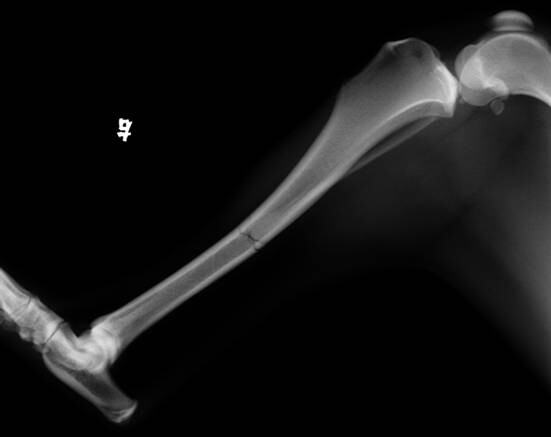

2 X光检查

X光侧位显示胫骨骨干骨折